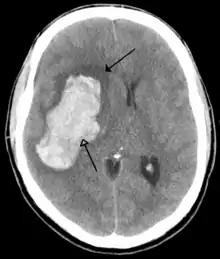

Injuries to the nervous system include brain injury, spinal cord injury, and nerve injury. Trauma to the brain causes traumatic brain injury (TBI), causing "long-term physical, emotional, behavioral, and cognitive consequences". Mild TBI, including concussion, often occurs during athletic activity, military service, or as a result of untreated epilepsy, and its effects are typically short-term. More severe injuries to the brain cause moderate TBI, which may cause confusion or lethargy, or severe TBI, which may result in a coma or a secondary brain injury. TBI is a leading cause of mortality.[47] Approximately half of all trauma-related deaths involve TBI.[12] Non-traumatic injuries to the brain cause acquired brain injury (ABI). This can be caused by stroke, a brain tumor, poison, infection, cerebral hypoxia, drug use, or the secondary effect of a TBI.[48]